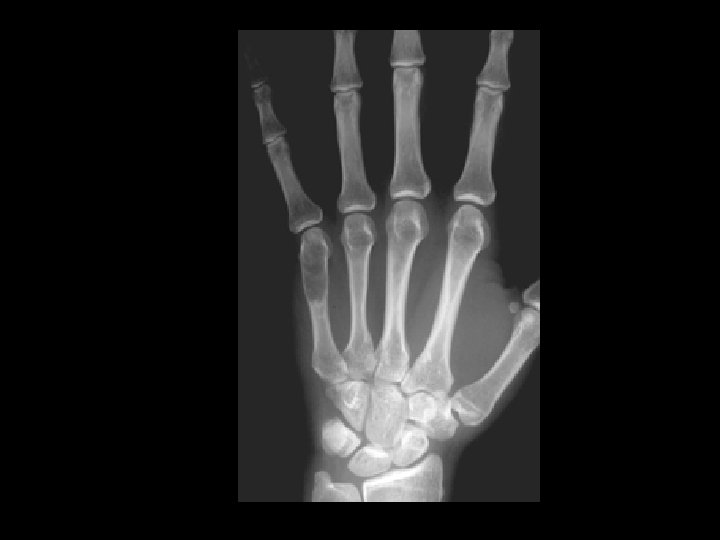

Enchondroma • Findings: – Lucent, slightly expansile lesion of the fifth MC • ddx: – Giant cell tumor – UBC – Fibrous dysplasia